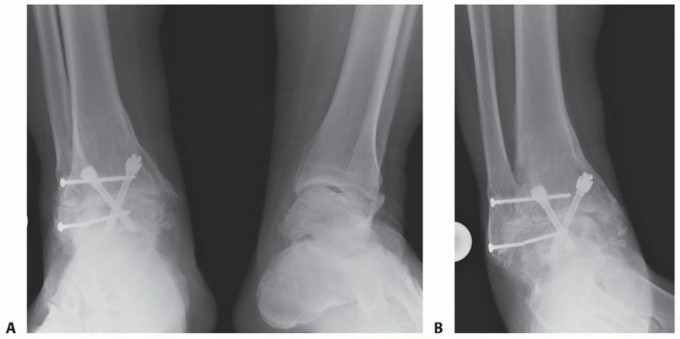

DEFINITION Subluxation or dislocation of the peroneal tendon is a relatively uncommon injury, with the majori…